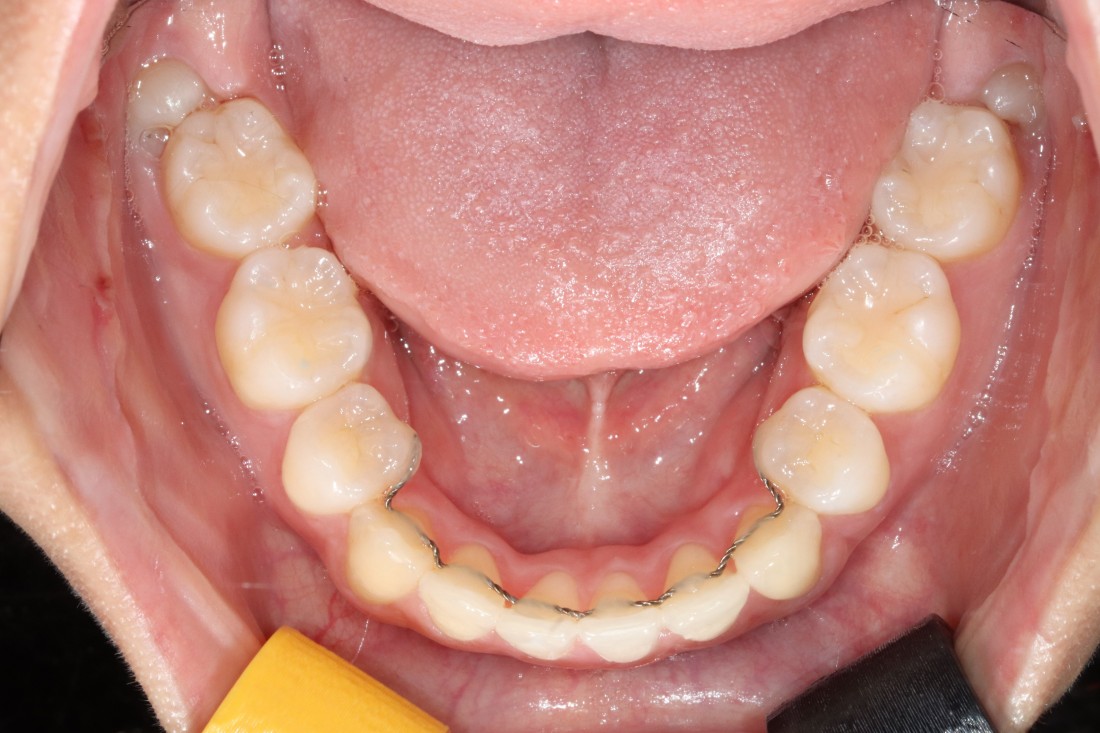

광주 교정치과에서는

교정 전 정밀검사 비용,

발치비용,

교정장치 (클리피씨) 비용,

월 진료비용,

유지장치 비용 등

교정진료에 필요한

모든 비용을 포함하여

추가금이 발생하지 않도록

합리적인 교정가격으로

진료하고 있습니다.

교정 진료 기간은

개인별로 치아 이동속도의 차이 때문에

예상기간보다 늘어날 수 있어서

월 3만원~5만원 사이의

월 진료비용이 발생하게 되면

금방 수십만원의 비용부담이 될 수 있기 때문에

월 진료비용을 받지 않고 있으며

정기검진을 편한 마음으로

예약 시간에 맞추어 오시면 됩니다.